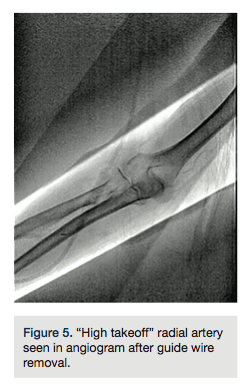

The right radial artery was punctured using counter-puncture technique and a .021-inch micropuncture guide wire was placed in the Teflon cannula. Mild difficulty was encountered at the first attempt to advance the wire. The guide wire was withdrawn and a low-pressure manual injection radial angiogram was performed. A perforation was noted at the distal radial artery (Figure 1). In an attempt to obtain control of the radial artery lumen, a .014-inch guide wire was placed in the access cannula and attempts were made to navigate the lumen, with further resistance. A new area of perforation was noted proximal to the previous site of extravasation (Figure 2). After several attempts, the .014-inch guide wire was placed in the subclavian artery successfully. Tortuosity was noted all along the proximal vessels (Figure 3).

But, more significant is the issue of fully utilizing the information we frequently have in the catheterization suite to potentially prevent some of these complications. When faced with a complication, we frequently fail to notice and utilize some of the details we would normally pay attention to. In this instance, when the operators performed a radial artery angiogram, only the radial and median arteries were visualized (Figures 1 and 4), with no visualization of the ulnar artery. This should have served as a hint that an anatomic variation could exist, and should have led to further delineation of the anatomy, after the lumen was accessed with a guide wire successfully. The other hint that anatomy conducive to severe spasm might exist was the fact the “tortuosity” was deemed severe enough to necessitate using a guide wire to torque the catheter for coronary access. These subtle hints are frequently not attended, and may lead to nerve-wracking complications as in this instance of entrapment. It is evident in the angiogram performed after guide wire removal that this patient did have a “high takeoff” radial artery (Figure 5), known to develop diffuse and severe spasm, creating a perfect environment for entrapment. In the hands of an experienced operator, most of the time severe spasm occurs in the setting of anatomic abnormalities.